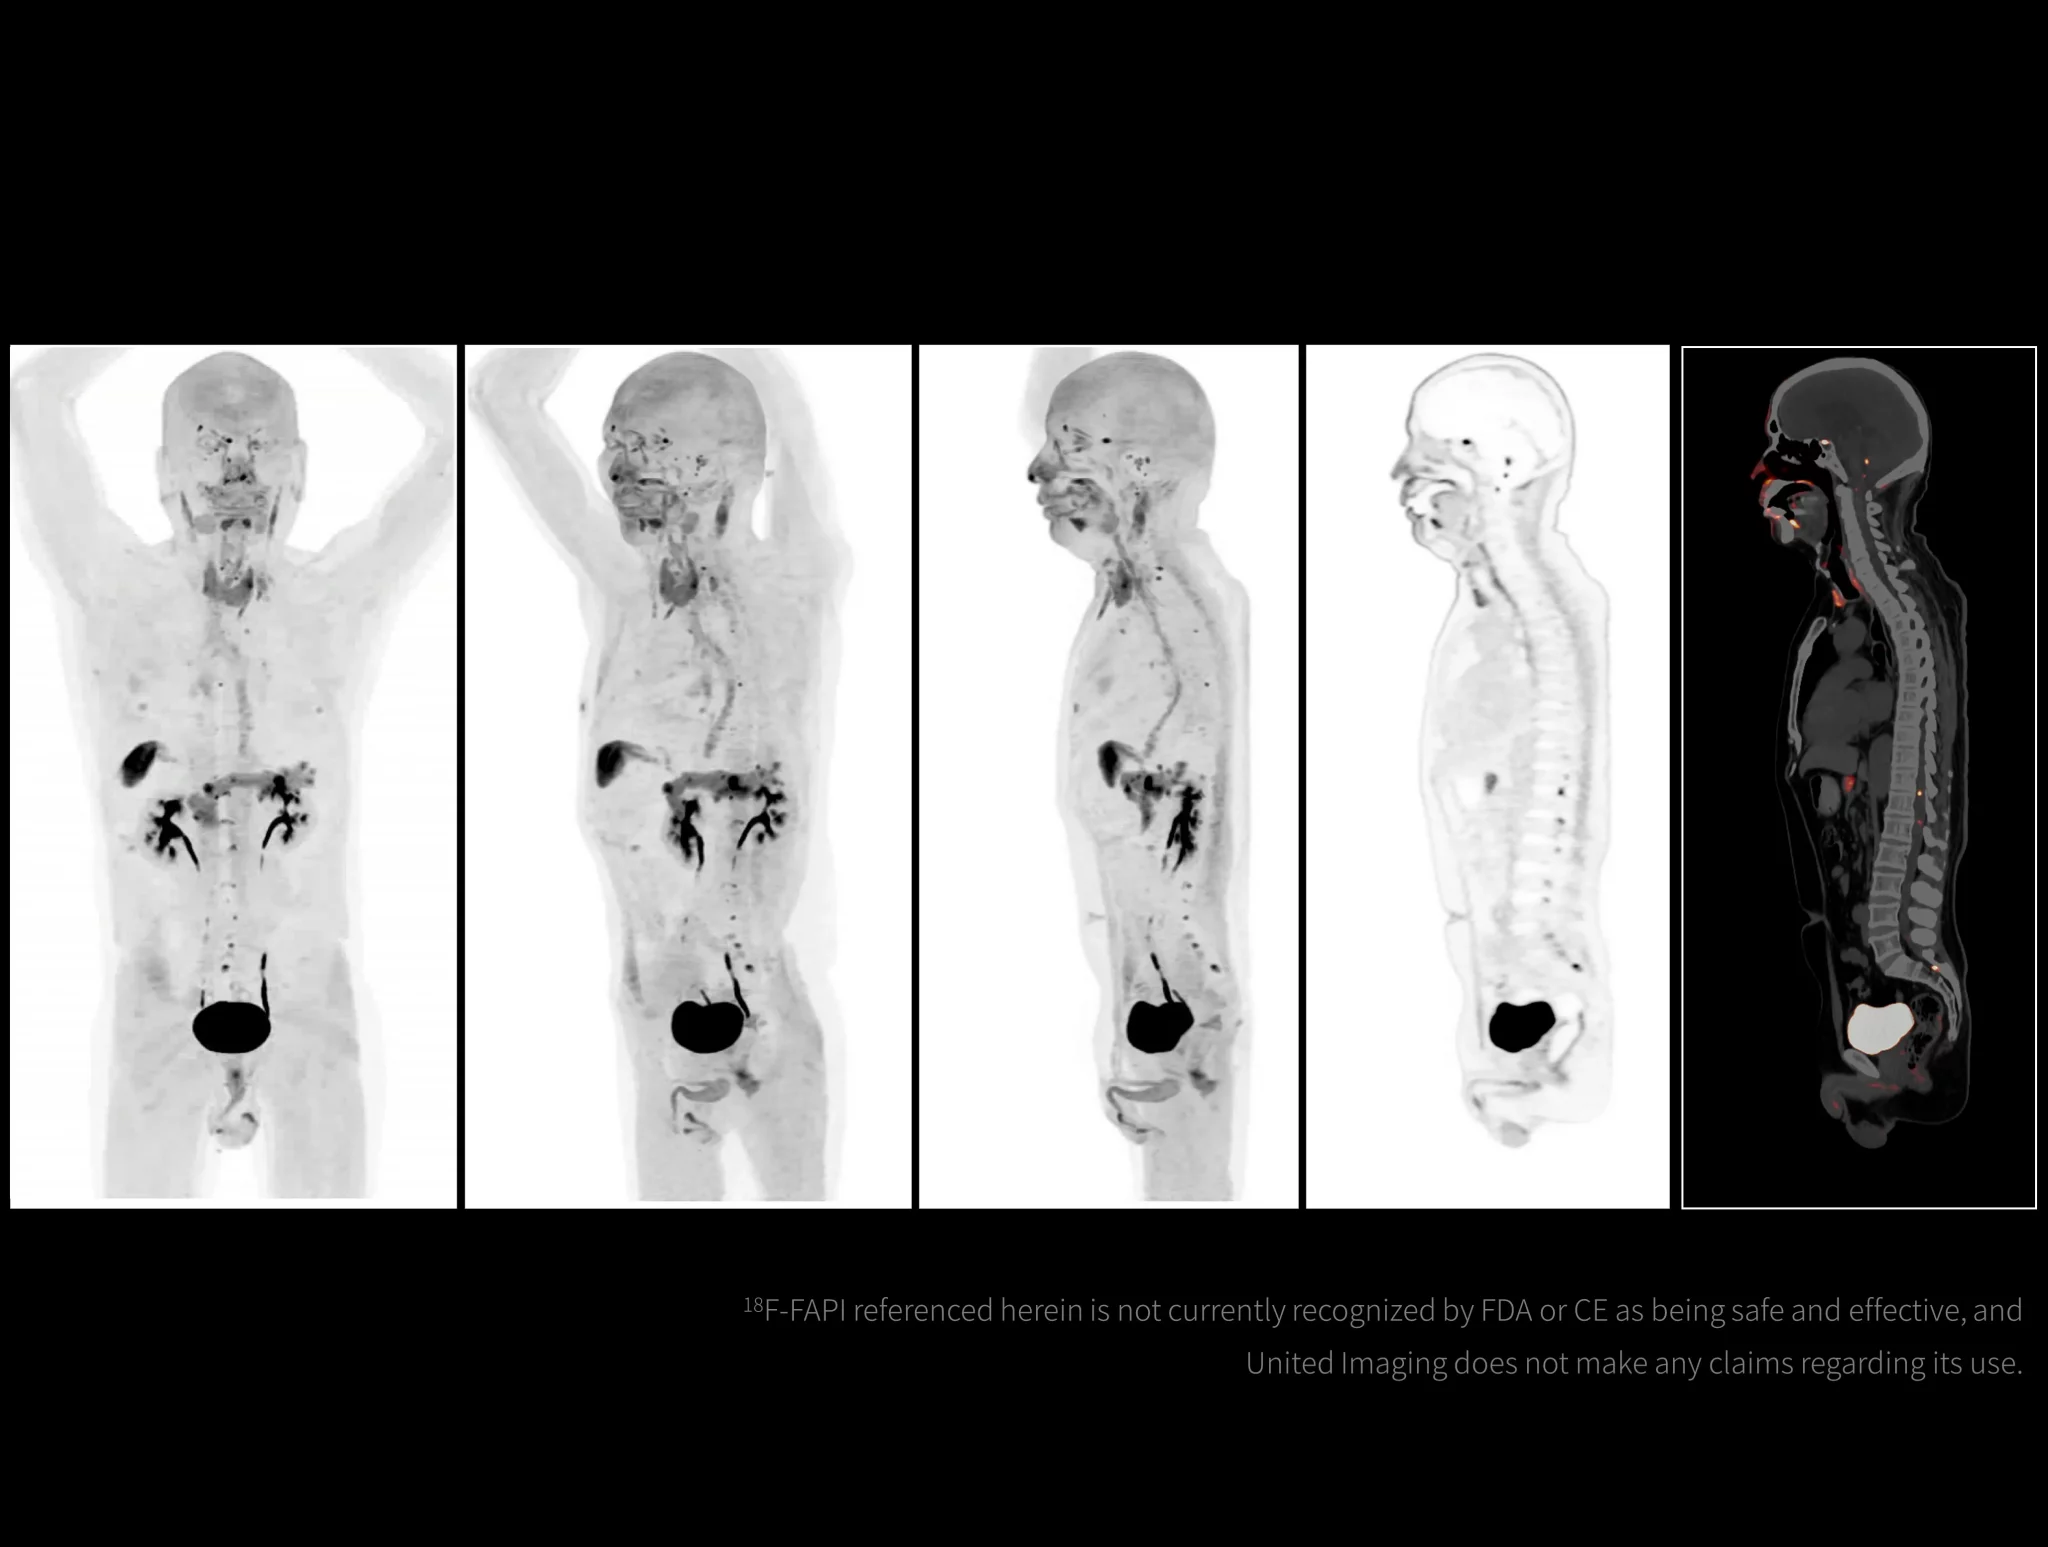

With the ultra-high system performance, uMI Panorama faces up to the challenges of tracers with different half lives and the complex scanning conditions, without compromise for image quality.

New-Tracer Imaging

Click on different tracers to see the images.